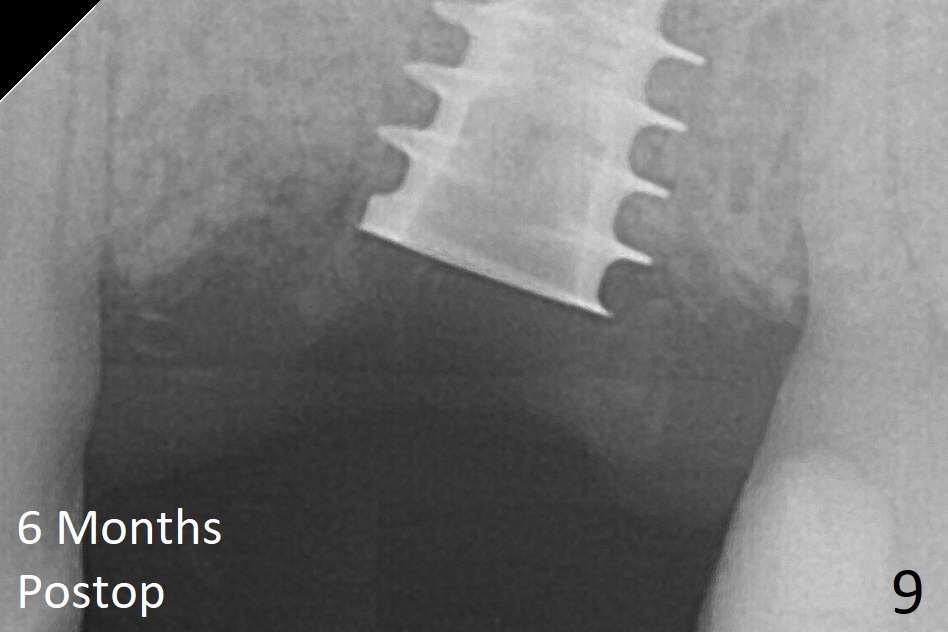

The implant is mobile 4 months postop (Fig.6).  A 6x2 mm healing abutment is placed next.  Although the implant remains mobile 6 months postop, the bone seems to have become denser around the implant (Fig.7-9).  A healing screw is placed.  When the bone height is limited (<7 mm), place a larger implant (>5.5 mm).  The implant seems to have osteointegrated 8 months postop (Fig.10).  Impression is taken following placing a 6.5x4(3) mm abutment.  The patient reports pain after cementation, which is less when the abutment screw is loose (9.5 months postop, 2 weeks post cementation).  CBCT taken after placement of a healing screw apparently shows loose bone mesial and distal to the implant (Fig.11 *).  The implant trajectory is less favorable.  It seems necessary to change to a large implant with more sold threads (Fig.12).